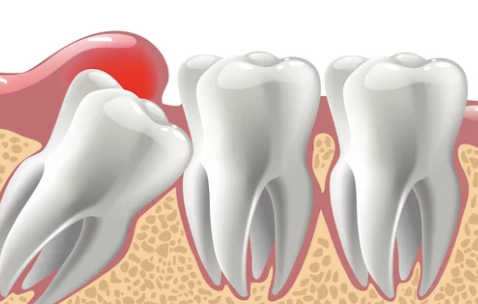

매복 사랑니의 의미

사랑니가 잇몸 아래에서 정상적으로 자라지 못하고, 잇몸 안이나 다른 치아에 눌려 비정상적인 방향으로 자라는 상태를 매복 사랑니라고 합니다. 매복의 정도는 다음과 같이 나뉩니다:

- 부분 매복: 사랑니 일부가 잇몸 밖으로 나와 있는 상태.

- 완전 매복: 사랑니가 완전히 잇몸 아래에 매복된 상태.

1) 주변 치아 손상 예방

- 매복 사랑니는 바로 앞 치아(제2대구치)를 밀어내거나 손상시킬 수 있습니다.

- 장기간 방치 시 인접 치아의 뿌리가 손상되거나 충치가 발생할 수 있습니다.

2) 감염 및 염증 예방

- 부분 매복 상태에서는 잇몸 주위에 음식물 찌꺼기가 쉽게 쌓여 염증(치주염)이 생기기 쉽습니다.

- 염증이 심해지면 농양이나 심각한 잇몸 감염으로 이어질 수 있습니다.